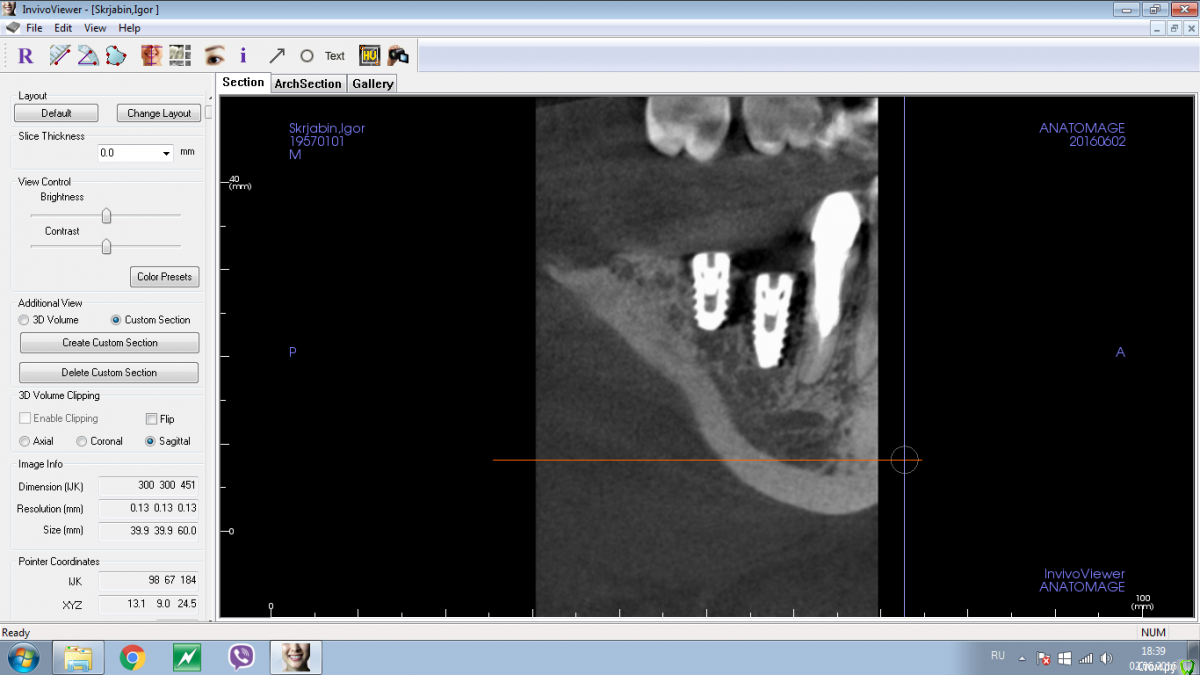

Shakirbura Опубликовано 2 июня, 2016 Поделиться Опубликовано 2 июня, 2016 Коллеги! Неделю назад поставили МИСы. Дистальный еле зашел, хотя сверлился до финишного, так и не смог полностью закрутить, остался оголенным язычно медиально. На снимках вроде бы видно (около 1,5 мм). Как быть? Переставлять пока не прижился? Если переставлять то куда засверливаться? Чет грустно совсем мне Ссылка на комментарий

dok1 Опубликовано 2 июня, 2016 Поделиться Опубликовано 2 июня, 2016 Не грустите. Я б переставился. И изначально наверное расщипился бы слегка для пущей надёги. Чисто имхо. И не по центру слегка вы засверлились. Не вижу где нерв. Мож длиннее можно было? Если длиннее можно, то сразу бы вкрутил новый. Если это предел - то подождал бы слегка. Вот тока сёдня в такую же историю попал. Трижды извлекал имплант и досверливал. И фреза зараза идёт на нужную глубину, а шуруп недокручивается. Но всё ж победил. Заглубился как хотел. Ссылка на комментарий

Shakirbura Опубликовано 2 июня, 2016 Автор Поделиться Опубликовано 2 июня, 2016 А в чем была проблема? Что значит "не смог закрутить"?Сверлил до последней фрезы, а стал закручивать - на половине застрял. Достал еще посверлил, начал крутить вперед-назад, вперед-назад и вот как то так поставил. Ссылка на комментарий

колесников Опубликовано 3 июня, 2016 Поделиться Опубликовано 3 июня, 2016 застрял в кортикалке имплант,резьба агрессивная. смело ставьте 10мм и притопите. вестибулярно у шейки напряжение,надо пройти ниже плотной кости. используйте развёртку и мечик в верхней трети. Ссылка на комментарий

Nazim_NV86 Опубликовано 3 июня, 2016 Поделиться Опубликовано 3 июня, 2016 (изменено) Сверлил до последней фрезы, а стал закручивать - на половине застрял. Достал еще посверлил, начал крутить вперед-назад, вперед-назад и вот как то так поставил. вы просто недосверлили упёршись ограничителем сверла в один край ложа. При этом пытались заглубить имплант относительно другого края,который пониже. В следующий раз возьмите фрезу на шаг длиннее. С опытом всё пройдёт. Привыкайте к своим имплантам и набору. Изменено 3 июня, 2016 пользователем Nazim_NV86 2 Ссылка на комментарий